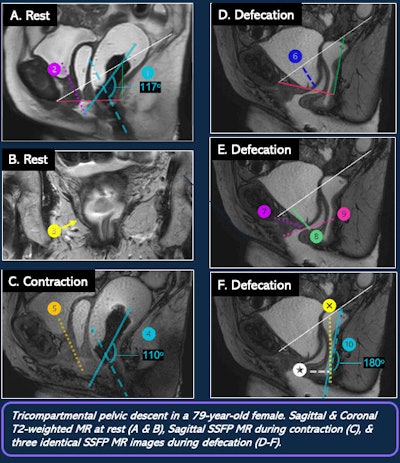

MR defecography exam on a 79-year-old woman.

Anatomic relationships within the compartments can be described further with the pubococcygeal line (inferior pubic symphysis to the most inferior coccygeal joint plane of levator muscle/pelvic floor), H-line (symphysis to posterior anorectal junction, anteroposterior diameter of levator hiatus, < 6 cm normal), and M-line (perpendicular to pubococcygeal line and intersects posterior H-line, reference for descent of hiatus, < 2 cm considered normal).